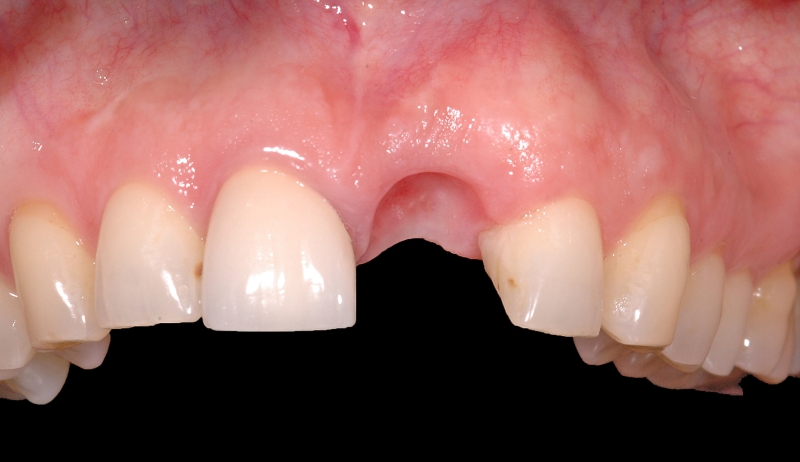

1/18 - Longitudinal fracture on the root resected tooth 21 with visible buccal fistulaGBR together with soft tissue augmentation with mucoderm® and maxresorb® - Dr. S. Scherg

2/18 - Obvious loss of the buccal lamellaGBR together with soft tissue augmentation with mucoderm® and maxresorb® - Dr. S. Scherg